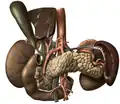

![]() Anatomy of the human pancreas | |

The pancreas is an organ that in humans lies in the abdomen, stretching from behind the stomach to the left upper abdomen near the spleen. In adults, it is about 12–15 centimetres (4.7–5.9 in) long, lobulated, and salmon-coloured in appearance.[7]

Anatomically, the pancreas is divided into a head, neck, body, and tail. The pancreas stretches from the inner curvature of the duodenum, where the head surrounds two blood vessels: the superior mesenteric artery and vein. The longest part of the pancreas, the body, stretches across behind the stomach, and the tail of the pancreas ends adjacent to the spleen.[7]

Two ducts, the main pancreatic duct and a smaller accessory pancreatic duct run through the body of the pancreas. The main pancreatic duct joins with the common bile duct forming a small ballooning called the ampulla of Vater (hepatopancreatic ampulla). This ampulla is surrounded by a muscle, the sphincter of Oddi. This ampulla opens into the descending part of the duodenum. The opening of the common bile duct into main pancreatic duct is controlled by sphincter of Boyden. The accessory pancreatic duct opens into duodenum with separate openings located above the opening of the main pancreatic duct.[7]